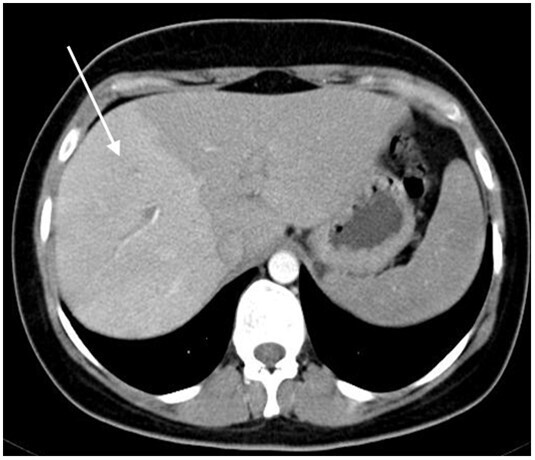

Rehaussement au temps artériel

Le foie est perfusé par la ou les artères hépatiques et la veine porte, celle-ci étant responsable d’environ trois quarts des apports sanguins. Les deux systèmes vasculaires se rejoignent pour perfuser le réseau sinusoïdal du foie. Il a été démontré qu’une baisse de la perfusion portale entraîne une augmentation compensatoire de la perfusion artérielle hépatique. Cet effet, parfois appelé «  effet tampon  », se traduit directement en imagerie par un hyper-rehaussement à la phase artérielle dans les territoires souffrant d’une baisse du débit sanguin portal.8 C’est un signe clé pour évoquer une maladie vasculaire du foie. L’hyper-rehaussement présente des limites nettes, respectant les territoires vasculaires (fig. 1). En cas de chute de la perfusion porte dans tout le foie, ce rehaussement est présent dans les régions sous-capsulaires. Il s’homogénéise aux temps veineux. La mise en évidence de ce signe doit faire rechercher toute cause de baisse de la perfusion portale (thrombose, compression, maladie microvasculaire, etc.).